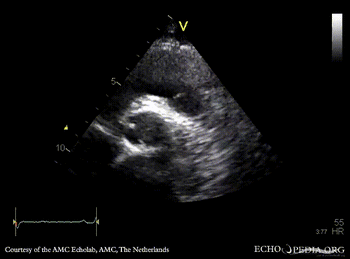

Davids procedure

Courtesy of: AMC Echolab, AMC, The Netherlands

PSAX: native aortic valve and prosthesis in ascending aorta PSAX with Color Doppler